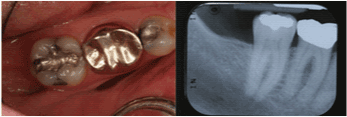

| Mandibular Right Second

Molar |

5 |

52.0% |